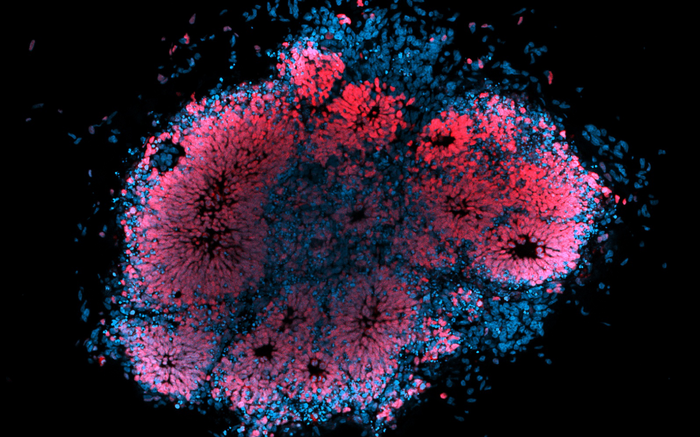

Microscopic image of human brain organoid infected with Zika virus.

Dr Julio Aguado (AIBN, UQ)